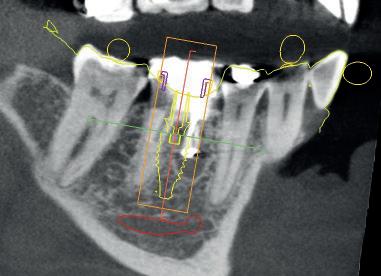

Synergy, as defined by the Cambridge Dictionary, is ‘the combined power of a group of things when they are working together that is greater than the total power achieved by each working separately’. When carrying out surgical procedures it is important that you use equipment solutions developed to offer a synergistic approach to your surgical processes. The equipment and instruments used should work in harmony to allow you to provide top quality treatment.

When it comes to synergy in dental implant procedures, such an approach often enables dental professionals to achieve better accuracy during the surgical phase. For instance, guided implant surgery utilises computer-generated surgical guides to enhance the precision of implant placement. By combining 3D imaging technology with specialised surgical instruments, dental clinicians are able to carefully plan the position, angle, and depth of the dental implant prior to the actual surgery. This collaborative effort between advanced imaging software and specialised instruments ensures that the implant is placed precisely in the desired location, leading to better aesthetic outcomes and increased patient satisfaction.

Seamless integration

Another advantage of instrument synergy in dental implant procedures is the reduced risk of surgical complications. Using specially designed surgical instrument and handpieces, allow dentists to ensure that they have everything necessary and readily available during a procedure. This allows the dental team to work efficiently and

effectively. The benefits of using compatible handpieces and equipment ensures that they can be seamlessly integrated into the surgical workflow, further reducing the time required for the procedure.

Seamless integration of instruments in dental implant procedures can also improve patient comfort and reduce recovery time. Advanced technology, such as piezoelectric instruments using ultrasound technology, offers precise and controlled cutting of bone, minimising trauma to the surrounding tissues. This means that patients experience less pain, swelling and bruising post-surgery, leading to a quicker and more comfortable recovery. Additionally, the combined use of specialised instruments, such as tissue punches and implant placement tools, allows for minimally invasive techniques that preserve the integrity of soft tissues. By reducing damage to the surrounding structures, patients experience less post-operative discomfort and achieve quicker healing.

clinical toolkit. Utilising the Piezomed improves procedure outcomes and results for patients as it is gentle on soft tissue ensuring reduced patient discomfort and quicker healing. For those placing implants measurement of osseointegration is ideal as it allows them to monitor the dental implants to inform loading decisions and ensure success. The Osstell Beacon from W&H, gives dental professionals peace of mind as they can measure and evaluate the stability of the implant ensuring full osseointegration, helping to reduce treatment times and avoid rejection in high-risk patients.

Working with equipment and instruments from top quality suppliers like W&H, who offer a highly synergistic approach based on many years of research, development and surgical know-how, allows for the best possible treatment outcomes. The Piezomed provides dental professionals with the benefits of innovative piezosurgery. By using the high-quality system, clinicians can remove only the targeted bone with precision, leaving the surrounding soft tissue and bone undamaged. The Piezomed module integrates seamlessly with the Implantmed Plus surgical unit, this flexibility between the Implantmed with surgical handpieces and the Piezomed creates a superior workflow driven solution for oral surgery, guiding the clinician through the cycle from implementation to evaluation. With W&H’s synergistic approach, which includes the use of the Implantmed, with the range of surgical handpieces, alongside the Piezomed the dentist benefits from an incredibly versatile

Overall, a synergistic solution to dental implant procedures offers numerous advantages that enhance the overall success of these procedures. Patient comfort is improved through the use of advanced instruments that minimise trauma and promote faster healing. With these advantages in mind, it becomes clear that dental implant procedures require wellthought through planning and the correct equipment. This helps to develop a solution which allows the clinician to provide high quality treatment enabling them to deliver patients with effective, efficient, and longlasting solutions for missing teeth.